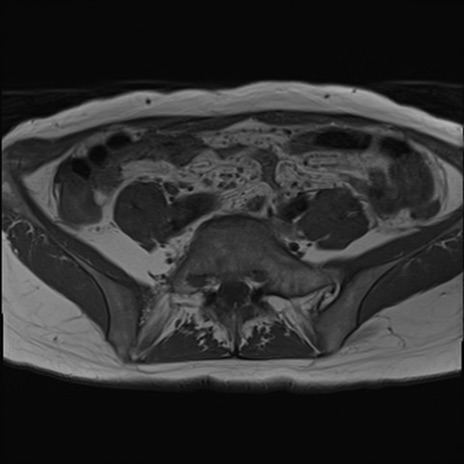

症例39 T1WI(横断像)

【症例】40歳代女性

【主訴】上下腹部痛

【現病歴】2日目から下腹部痛あり。夜間は痛みで眠れなかった。昨日より上腹部痛と下痢が出現。臥位で痛みは軽快したため、休んでいた。本日になって臥位でも立位でも痛みが強くなってきたため救急要請。

【既往歴】子宮内膜症

【身体所見】部:平坦・軟、左上下腹部に圧痛あり、反跳痛あり。

【データ】WBC 21800、CRP 26.78

MRI(4日後)